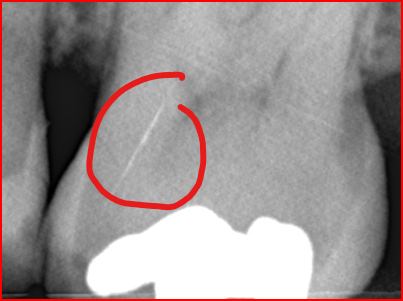

Ik zie mogelijk een verbreed parodontaal spleet ( lijn tussen kies en tandvlees voor de leek) in de 25. Lijkt op een "diepe"vulling (dicht bij de zenuw)... hoe test de 25...Bij twijfel kan je eventueel proef boren zonder verdoving maar dat is niet altijd betrouwbaar. Knarst u??.

Maar even voor mijn beeldvorming. Sensaties kwamen vanaf rechterkies (verstandskies)Plus die links ernaast. Element 25 is de 3e van links toch? Proefboren is een optie maar foto ondersteund geen ontsteking toch of mis ik nu iets ?

Ah zo! Zo heb ik niet over nagedacht. Die kan die pijn en naar naar 26 en 28 kunnen veroorzaken? Helder. Ben vorige week maandag consistent met tandpasta repair van elmy begonnen en paar dagen erna pijn maar ook sinitus. Pijn is helemaal weg sinds eergisteren. Dus ik twijfel nu. Necrose of die spleet. Element 25 geen indicatie van Necrose?

Uiteindelijk was ik in het buitenland en kreeg ik weer last. Uiteindelijk cbtc scans gedaan en microscopisch 4 kanalen. Was heftig lang. Geen verticale fracturen gevonden maar wel gevuld met glasvezel stiften. Dame werkte bij alldent in Frankfurt. Kroon vond ze met huidige stand niet nodig maar goed. Even je objectieve mening wat vindt je er van?. Ze was extreem secuur. Napijn wel met bijten maar was vanwege grote behandeling gebruikelijk. Kan nog even zeuren. Laesie was minimaal volgens haar.